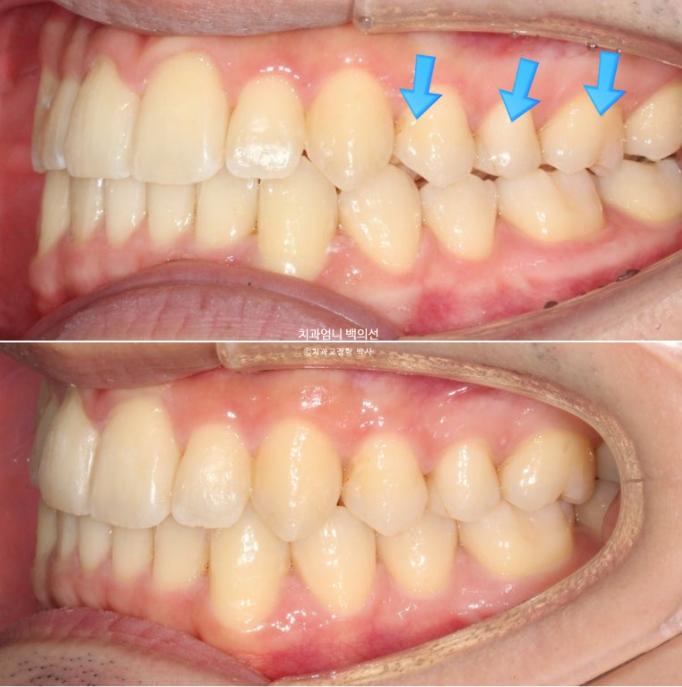

파란 화살표 부분이 치료 마무리 직후 논문대로 어금니 교합이 0.9mm떠있는 상태로 보시면 됩니다.

아래 사진은 2주간 교합 안정화 과정을 거쳐서 어금니가 잘 닿게된 모습입니다.